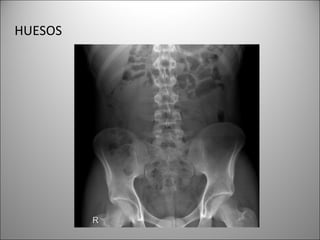

HUESOS